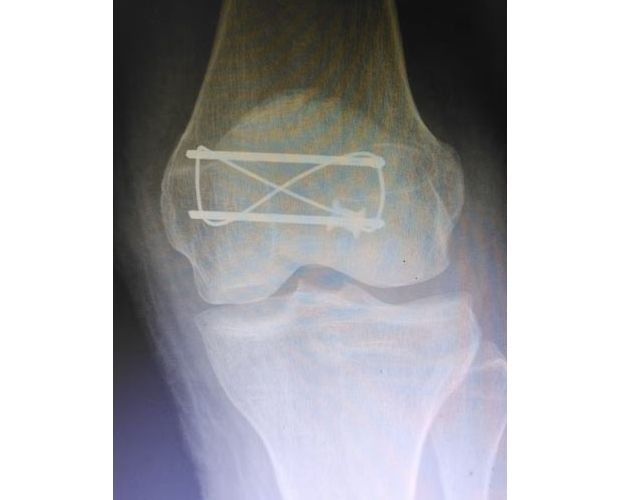

手术现场,徐三军主任凭借多年积累的临床经验和娴熟的手术技巧,精准完成骨折复位、钢板内固定、伤口缝合等一系列关键操作,动作规范流畅、精准高效,最大限度减少手术创伤。该院外科医护团队全程密切配合、协同发力,严格按照手术规范操作,全程严密监测患者心率、血压等生命体征,及时应对术中各类突发情况,全力保障手术安全。此次手术全程顺利,术中出血量少,患者生命体征始终平稳,术后患者顺利安返病房,为后续康复治疗奠定了坚实基础。

此次手术不仅是一次成功的临床救治实践,更是一堂生动鲜活的“实战教学课”。手术过程中,徐三军结合自身临床经验,同步向该院外科医护人员讲解髌骨骨折手术的操作要点、规范流程、风险防控技巧及术后康复核心要点,采取“手把手”带教、点对点指导的方式,耐心解答医护人员提出的疑问,帮助基层医护人员理清诊疗思路、提升操作能力。此次带教有效提升了卫生院外科团队在骨科手术及围手术期管理方面的专业水平,为基层医疗服务能力持续提升注入了强劲动力。